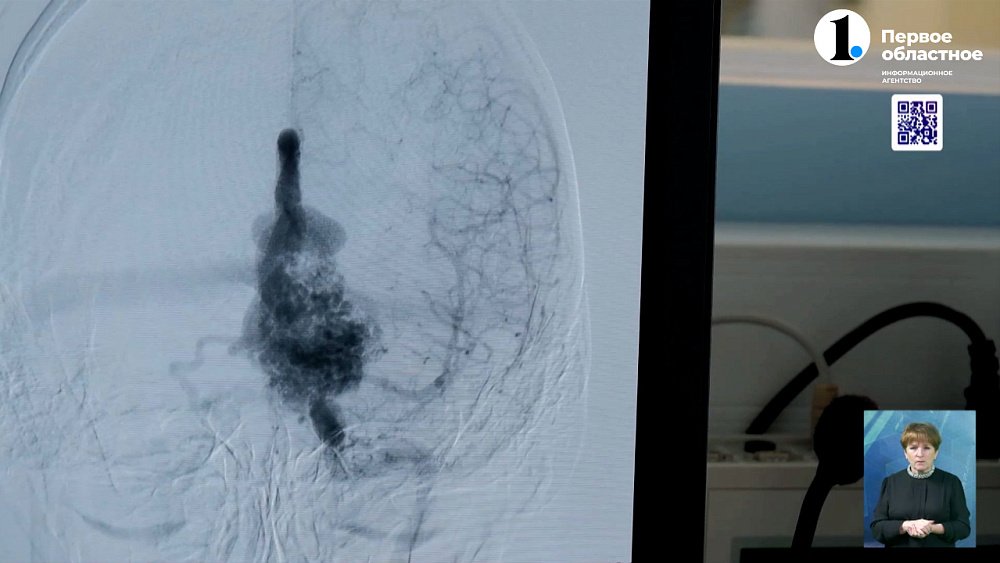

Екатерине Должено врачи провели клипирование сосудов головного мозга. То есть сделали так, чтобы они больше не расширялись. Женщину готовят к выписке. Случай Вячеслава Татаева куда более сложный. Несколько лет мужчина почти не чувствует запахи. Обращался к лору, но врач направил копейчанина к неврологу. Оказалось, проблемы с обонянием у Вячеслава из-за аневризмы.

Вячеславу Татаеву врачи провели трепанацию черепа. Удалили аневризму. И вскоре мужчина планирует увидеться с дочерью и внуком. В областной клинической больнице удаляют аневризмы южноуральцам еженедельно.

Сложность заболевания определяется расположением аневризмы. И ее размером. Чем она больше, тем сложнее будет операция. Трепанацию черепа, по словам врачей, проводят только с самыми крупными патологиями.